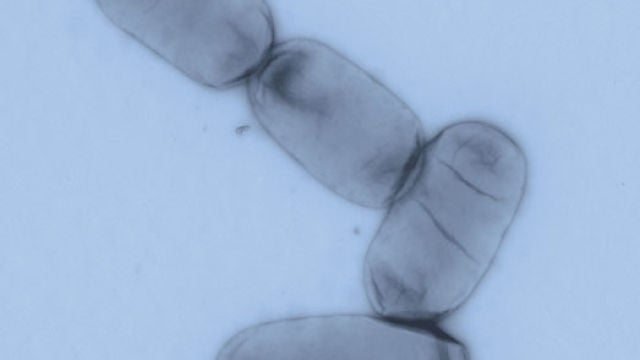

Salmonella enterica es uno de los principales patógenos entéricos tanto en países desarrollados como en regiones en vías de desarrollo.Sinc

Según los Centros para el Control y Prevención de Enfermedades (CDC), la salmonela es una bacteria que se puede encontrar en varios alimentos, como en las carnes de pollo, res, cerdo, en huevos, frutas, vegetales, y hasta en los alimentos procesados.